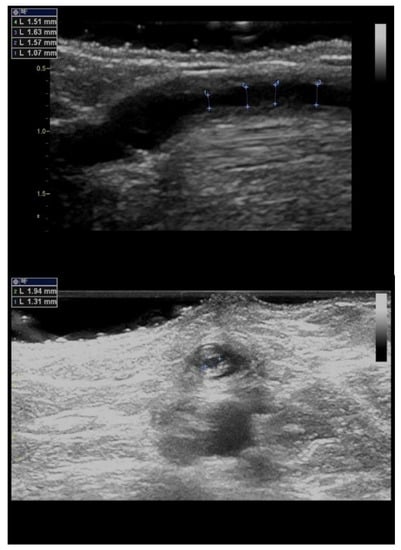

5. Significant Stenosis Definition by Ultrasonography

| Residual diameter < 1.9–2.0 mm | No additional criterion |